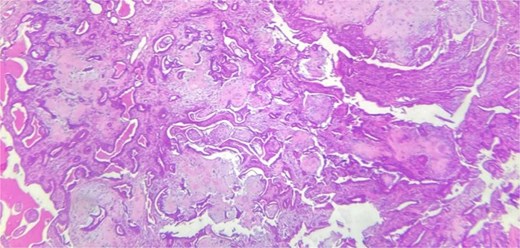

A 53-year-old Moroccan man, with no significant medical history, presented with a cheek swelling evolving over 6 months without associated symptoms. Clinical examination revealed a 1.7 cm cystic-like swelling in the cheek, suggestive of a ruptured epidermoid cyst. It was mobile and skin-colored, without inflammatory signs. Lymph nodes and salivary glands were normal. An excisional biopsy of the mass was performed. Macroscopically, it was a 1.7 cm beige, friable to firm, rounded nodule. Microscopic examination showed a well-circumscribed benign tumor proliferation composed of cysts, tubules, and ducts (Fig. 2), lined by a bilayered epithelium. The cells exhibited no nuclear atypia (Fig. 3). The fibromyxoid and chondroid stroma allowed for diagnosis without additional techniques. There was no perineural invasion or vascular emboli, and surgical margins were clear. Postoperative recovery was uneventful, and no further follow-up or additional examinations were necessary.

Benign tumor proliferation composed of cysts, tubules, and ducts.